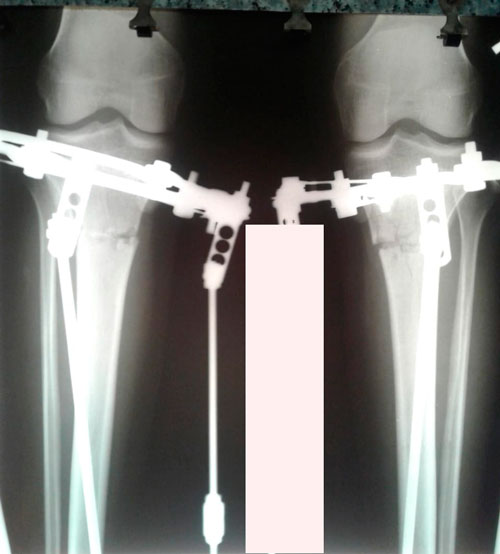

Рентген на фиксации(после исправления деформации ног)

Вложения